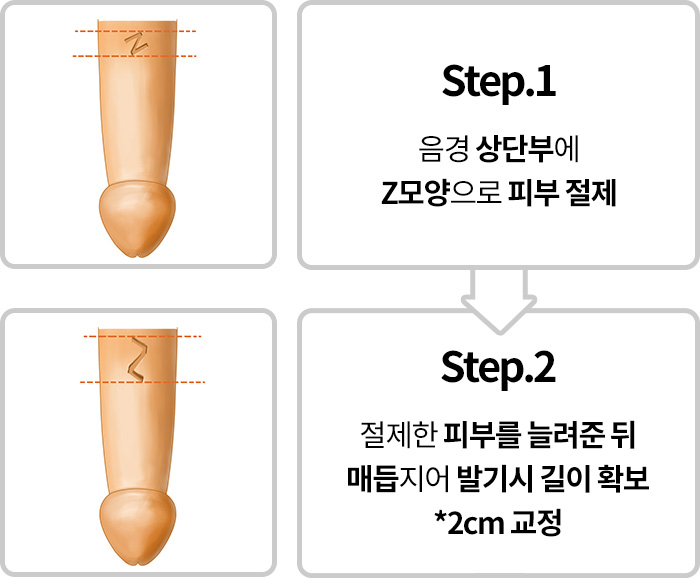

음낭갈퀴

음경에서 음낭으로 이어지는

피부가 마치 갈퀴모양처럼

발달되어 있는 경우

음낭갈퀴

음경에서 음낭으로 이어지는

피부가 발달되어 길이가 짧아 보이는 만큼

발달된 피부조직을 제거하는

수술을 통해 효과를 기대해볼 수 있습니다.